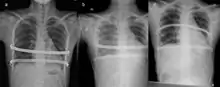

![]() X-Ray of a 15-year-old male after undergoing the procedure | |